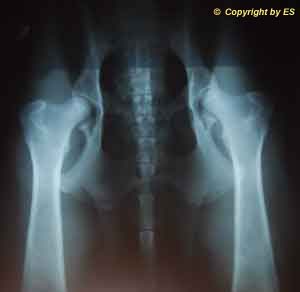

HD-ED Aufnahme  von Condor`s Hüfte vom 12.08.2014

HD normal, kein ED

Hüfte